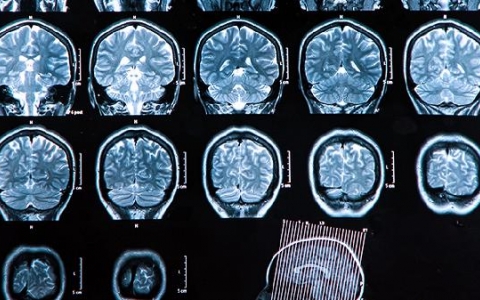

老人大面积脑梗死需住院多久

大面积脑梗死对于老年人来说是一个严重的健康问题,住院时间的长短取决于多种因素,包括病情的严重程度、患者的身体素质以及是否存在并发症等。如果患者意识清楚,生命体征

脑溢血第二次复发能治好吗

脑溢血第二次复发是否能治好,取决于多种因素,包括出血量、症状表现以及治疗时机等。如果出血量较少且症状不明显,通常通过积极治疗是有可能治愈的;但若出血量较大或已有

脑溢血昏迷30天还能醒吗

脑溢血昏迷30天是否还能醒来,这个问题需要根据具体情况来判断。通常情况下,脑溢血的严重程度、出血量、治疗时机以及患者的整体健康状况都会影响苏醒的可能性。对于一些